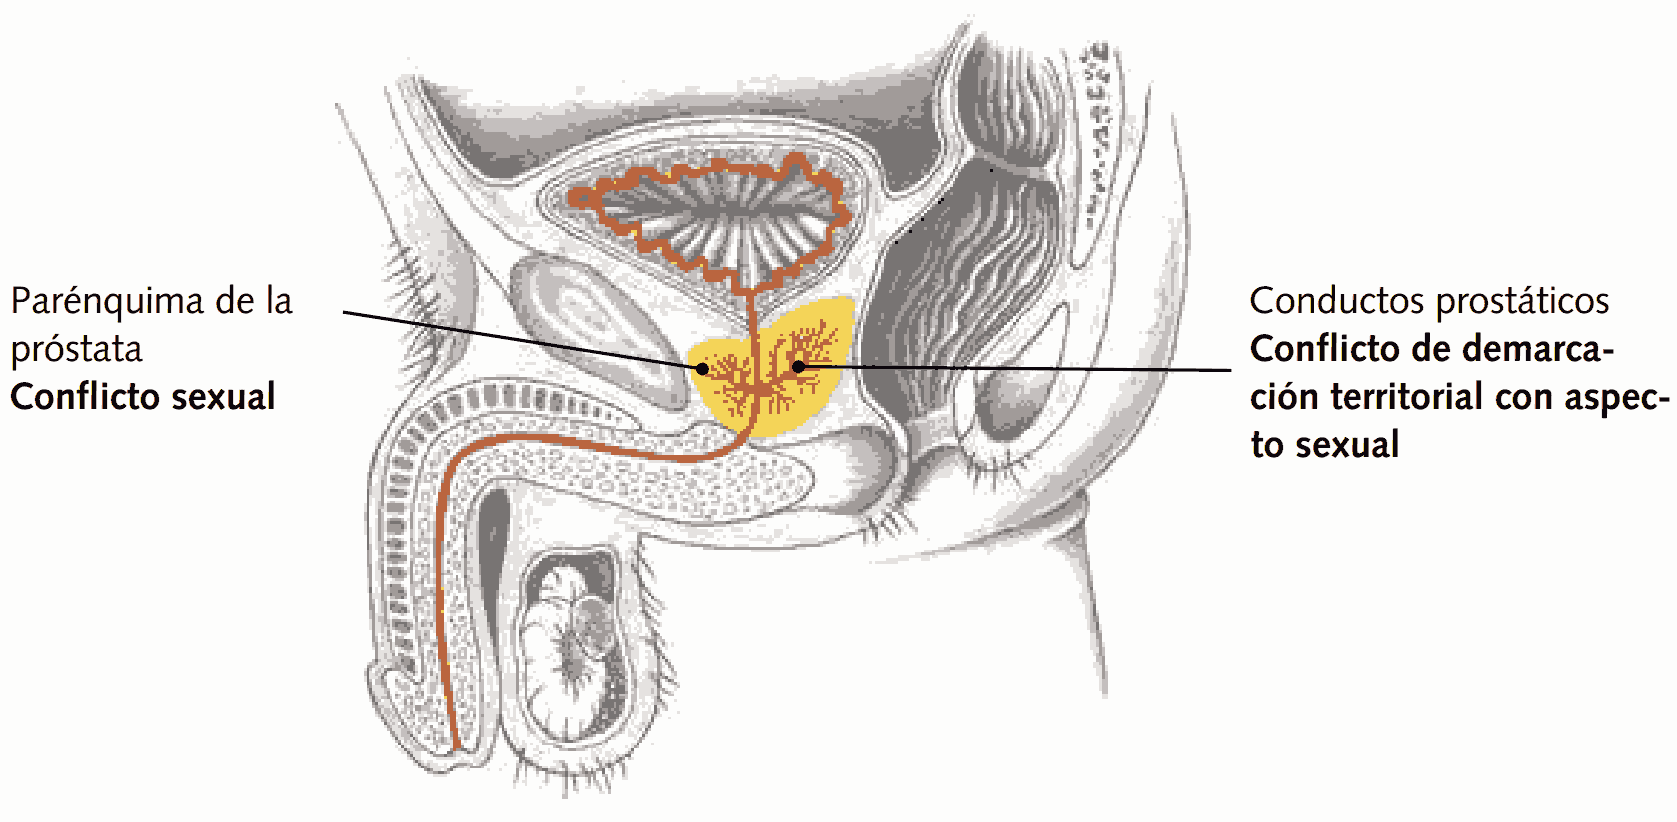

SBS del parénquima de la próstata

Agrandamiento de la próstata (hiperplasia prostática), cáncer de próstata (adcar.)

Conflicto biológico

1. Conflicto sexual. No poder o no deber reproducirse. No sentirse lo suficientemente masculino (potente). Se tienen dudas sobre la propia masculinidad o capacidad de erección. Generalmente en hombres de edad más avanzada, que ya no reaccionan con conflicto territorial. (Dr. Hamer: “Conflicto semi-genital”).

2. Conflicto relacionado con la “misión del hombre” (satisfacer a la mujer, engendrar hijos )

3. Según Frauenkron-Hoffmann: Se piensa, que no se le está dando a los hijos el impulso o la madurez que necesitan en su camino (por ejemplo, estímulos, una buena formación, pautas de comportamiento).

Conflicto activo

Aumento funcional del tejido glandular de la próstata, crecimiento de un tumor prostático (adcar.) en forma de coliflor: crecimiento celular en las glándulas de la próstata, subida de los valores PSA. Expansión en la zona en caso de actividad de conflicto prolongada: obstrucción del flujo, dificultad al orinar.

Sentido biológico

Aumento en la producción de secreción prostática. El olor más pronunciado a almizcle en la orina y el esperma es para la mujer un indicador de potencia y disponibilidad reproductiva. Este puede mostrar su superioridad con más esperma. El macho de más edad puede mostrarle a la hembra que todavía no está “desfasado”. Una mayor cantidad de secreción prostática supone más “provisiones” para los espermatozoides en su camino.

Reparación/curación

Normalización del funcionamiento, reducción por caseificación tuberculosa que produce necrosis del tumor. Orina más turbia, fétida, en su caso con sangre. Dolores, inflamación (prostatitis), hinchazón, sudores nocturnos. Encapsulación del tumor sin síntomas, en caso de que no haya bacterias presentes. Con frecuencia, aunque no siempre, retención urinaria, ya que la próstata tiene espacio suficiente a su alrededor para ensancharse. En su mayoría es un conflicto recurrente.

SBS de los conductos prostáticos

Retención urinaria sin subida considerable del PSA (carcinoma prostático intraductal, neoplasia intraepitelial prostática o PIN)

Conflicto

Conflicto con aspecto sexual de no poder demarcar límites (combinación de conflicto de próstata y vejiga).

Flaccidez de la musculatura lisa anular de los conductos prostáticos (urotelio), solamente después se produce una pérdida celular en los conductos excretores, generalmente inadvertida: ensanchamiento del lumen.

La ancha musculatura anular permite una mejor entrega del secreto prostático para marcar territorio y para el “cortejo”, el olor a almizcle es señal para la mujer de potencia y disponibilidad reproductiva.

Reconstrucción del epitelio de transición. Hinchazón durante la reparación que provoca retención urinaria, orina residual. La neoplasia intraepitelial prostática (PIN) en la MC equivale a una reconstrucción del epitelio de transición. Rasgo importante: Sin valor de PSA elevado o con pequeña subida.

En su mayoría es un conflicto recurrente.